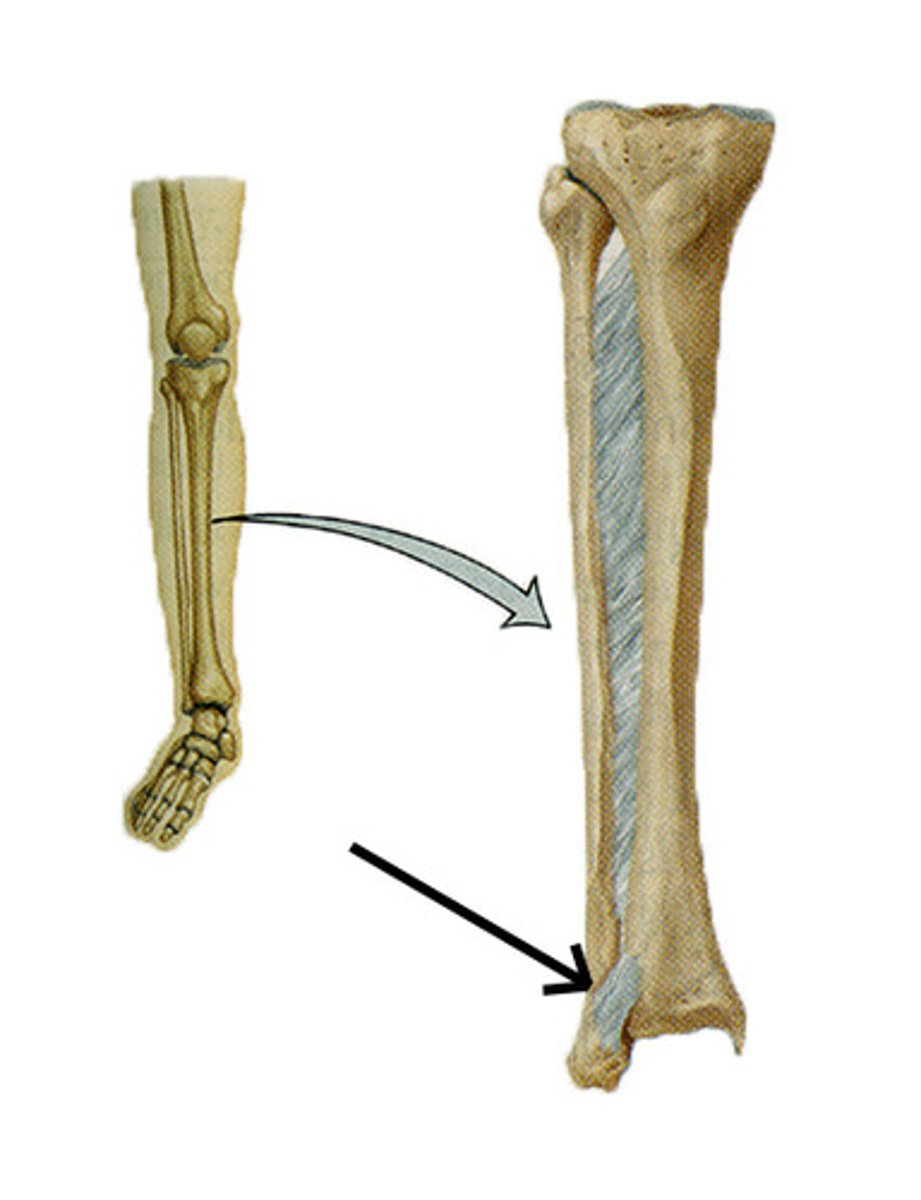

A majority of body weight is transferred through the (bone)

Tibia

What percentage of total body weight is transferred through the tibia?

90% total body weight